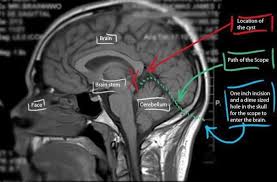

The diagnosis of pineal cyst is usually established by MRI with defined radiological criteria to distinguish benign pineal cyst from tumors of this area. A pineal cyst is usually only treated if it causes symptoms. In order to detect the presence of a cystic mass in the head magnetic resonance imaging is required.

Surgical interventions have been used to remove the cyst and resolve symptoms37 These approaches include both. Very few require surgery however.

Surgical removal is the most common treatment for pineal cyst. Pineal cysts tend to be more common in. The diagnosis of pineal cyst is usually established by MRI with defined radiological criteria to distinguish benign pineal cyst from tumors of this area. Surgical interventions have been used to remove the cyst and resolve symptoms37 These approaches include both. Some tumors are sensitive on radiationOutcome of the surgery depends on size and type of tumor. A neuro-ophthalmologist can be very helpful in defining vision and eye movement problems and can determine if these problems are related to the cyst. If symptoms are present your healthcare provider may recommend these treatments. Since your headaches might not be due to the pineal gland cyst discuss with your doctor other possible causes for your headaches. Pineal Cysts are fluid structures that form on the pineal gland and are treated when they are large greater than 2cm and cause symptoms such as debilitating headaches or eye movement problems.